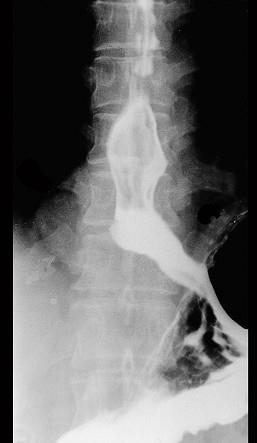

问题 男性患者,42岁,2年前始有吞咽梗阻感,近期又出现胸骨后压迫感,入院行X线钡餐检查,结果如图所示,最有可能的诊断是 ( )

选项 A、食管平滑肌瘤 B、贲门失弛症 C、贲门癌 D、食管憩室 E、食管癌

答案 A